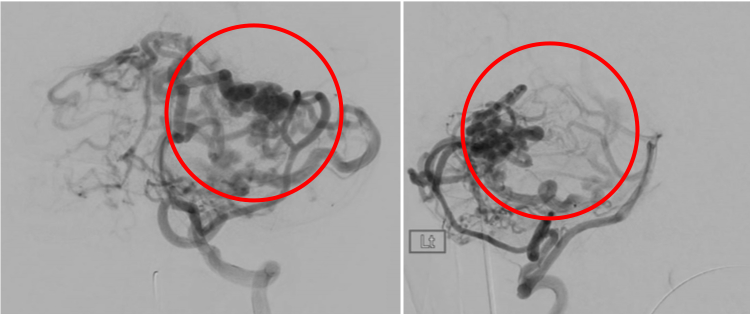

フローダイバーターステント留置術

通常のコイル塞栓術では不完全閉塞になりやすく、また再発の可能性が高いと考えられる大型の脳動脈瘤に対しては『フローダイバーターステント』を用いた治療を行います。

近年、中型の脳動脈瘤に対しても『フローダイバーターステント』での治療も行っております。

術前の造影写真です。〇内に脳動脈瘤が造影されています。

術直後の造影写真ではまだ脳動脈瘤は造影されています。

術直後の写真です。〇内は留置されたフローダイバーターステントです。

半年後の造影写真では脳動脈瘤は完全に消失しています。